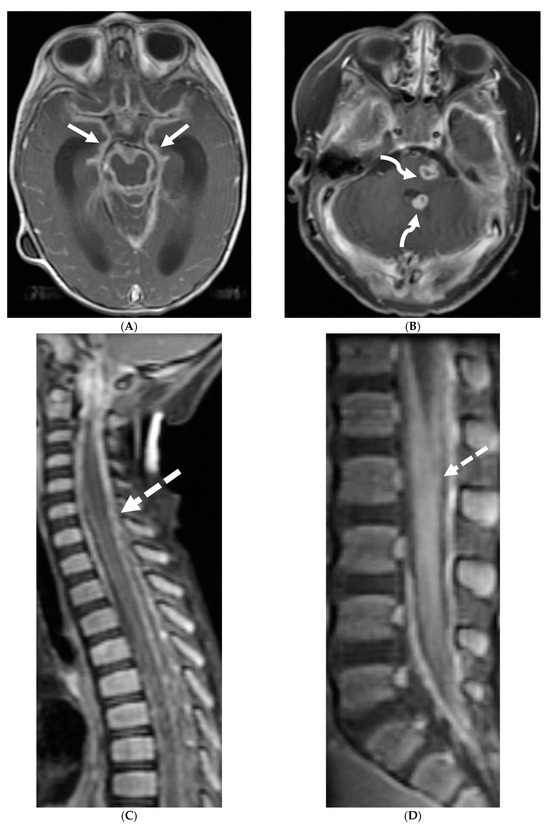

3.1. Protothecans

Prototheca species are unicellular algae that are typically known to involve the cutaneous and subcutaneous tissues in humans [6]. Systemic involvement, although rare, can cause meningitis, peritonitis, endocarditis, etc. and is commonly seen in immunodeficient individuals [7]. Prototheca spp. infections are usually exogenous and associated with traumatic inoculation from contaminated soil or water. They can also occur from surgery or catheterization, and even insect bites [8]. Exposure leads to chronic granulomatous inflammation with necrosis [6]. Notably, diagnosis of protothecosis may be challenging as it is not easily identified on Hematoxylin and eosin (H&E) or routine fungal stains, and mimics many fungal infections such as Coccidiodes, Blastomyces. Imaging findings include diffuse LME along the cortical sulci and spinal cord, with multiple loculations given the chronic inflammatory response. These loculations characteristically cause mass effect leading to a flattened and deformed spinal cord (Figure 2) [9].

Figure 2.

Post contrast sagittal T1 brain (A), T1 spine (B), axial T1 brain (C) and spine (D): 17-year-old girl with couple of years of fatigue, shuffling gait, back/lower extremity pain. There is moderate ventriculomegaly (white star). Meningeal enhancement is present around the cervical cord (white arrow). Flattened and deformed brainstem & spinal cord diffusely (curved arrows) and enhancing septae (dashed arrows) within the thecal sac are noted likely from chronic meningitis. Basal cistern enhancement (open arrow) and septae (arrow head) in the lateral ventricles likely reflects sequela of chronic inflammation/infection. Pathology: Prototheca Zopfil.